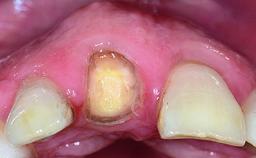

Replacement of a Failing Upper Left Central Incisor: Immediate Placement of an RC Bone Level Implant and Provisionalization

Abutment Type CAD/CAM

Prosthesis Type FDP

Loading Protocol Immediate

Retention Cemented, with prosthesis margin < 3mm submucosal Cemented, with prosthesis margin < 3mm submucosal

Provisional Implant-Supported Prosthesis Prosthodontic margin < 3 mm apical to mucosal margin Prosthodontic margin < 3 mm apical to mucosal margin